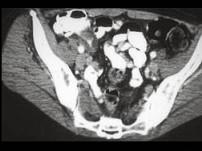

问题 男,42岁,右下腹痛、腹胀半年,无浅表淋巴结肿大,影像检查如图,最可能的诊断是 ( )

选项 A、肠结核 B、腹膜后纤维化 C、结肠癌 D、Crohn氏病 E、淋巴瘤

答案 D